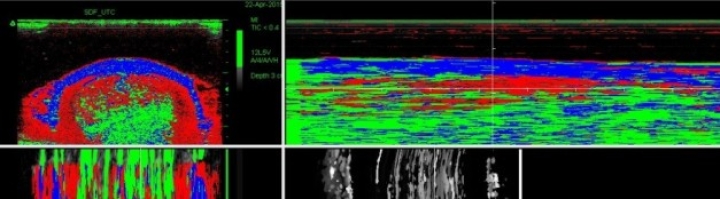

• UTC (Ultrasound Tissue Characterisation)

UTC | nieuwe publicatie op Paardenarts.nl

Publicaties

10 oktober 2015

1 min